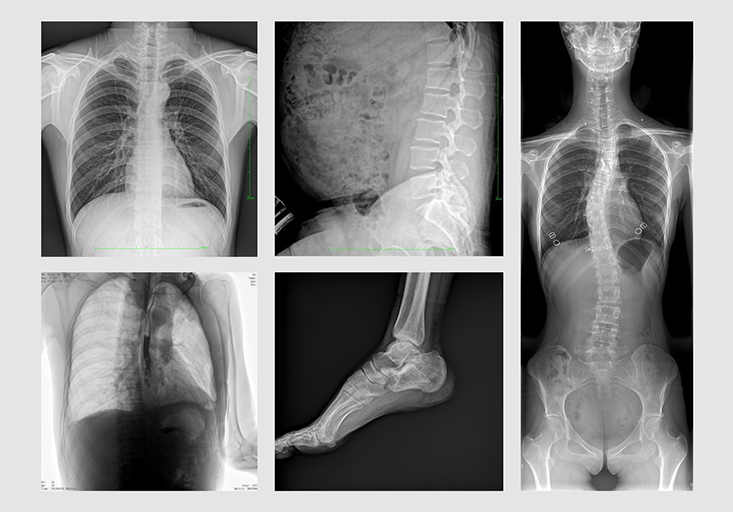

清晰的臨床圖像